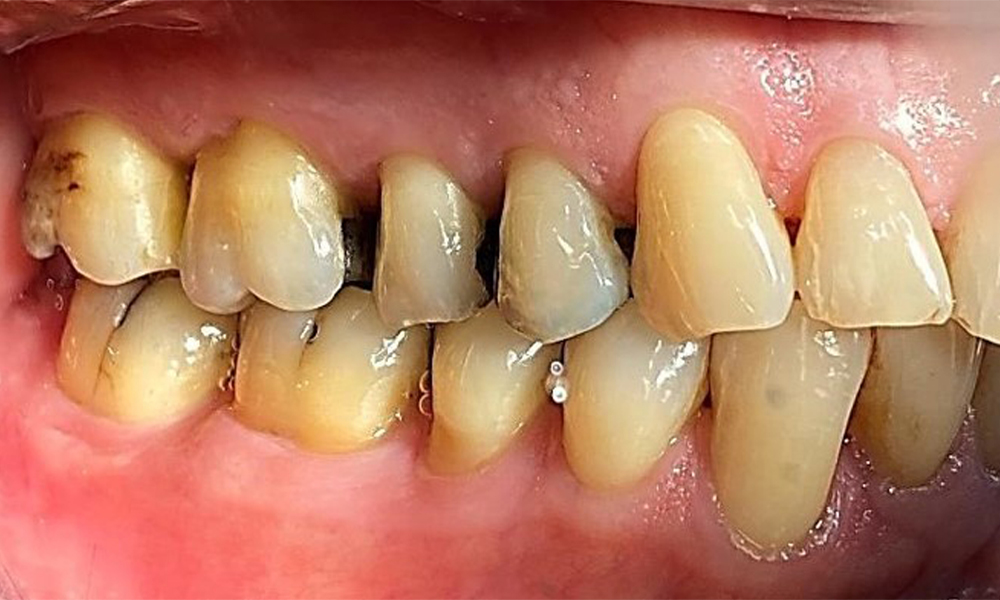

Right lateral view. Loss of the interdental papillae.

Fig. 3 Right lateral view. Loss of the interdental papillae. © Dr R. Krapf

The patient has a full dentition with 28 teeth, which includes amalgam and composite fillings in the molar and premolar regions. There is a visible clinical marginal gap present on tooth 14. Tooth 27 has an adequate gold inlay. There are also generalized attritions and abrasions. (Fig. 2, Fig. 3, Fig. 4, Fig. 5, Fig. 6)

Periodontal findings

The patient has stage II, grade B periodontitis (5). At 1 to 3 mm, the clinical probing depths were within the physiological range. Localized probing depths of 5 mm were observed on the mesiopalatal aspects on both 17 and 27. There are generalized recessions of 1–3 mm with partial loss of the interdental papillae (Fig. 2, Fig. 3, Fig. 4)